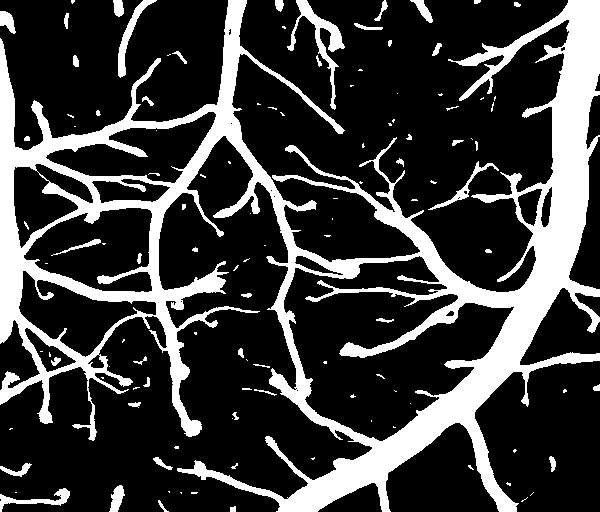

对比是否作光照补偿的二值化结果如下,可以,未作光照补偿时,二值化结果并不好,光照不均匀的地方本来是背景,也被划分为前景了。作了光照补偿则没有这个问题。

作光照补偿的二值化结果

本文介绍了针对光照不均匀图像的二值化处理方法,包括光照补偿、去噪、图像增强和最佳阈值迭代法获取阈值。通过计算背景信息、非局部均值滤波去噪、USM锐化图像增强以及最佳阈值迭代法,实现了在光照不均匀条件下的良好二值化效果。实验结果表明,光照补偿能够显著改善因光照不均导致的二值化问题。